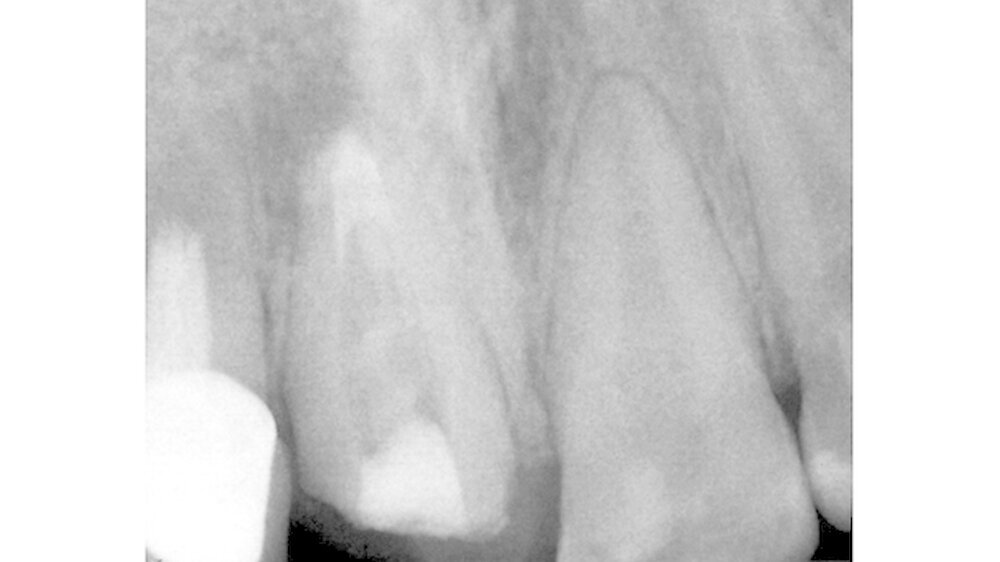

Im Verlauf der Behandlung wurden die prothetische Suprakonstruktion an 11 abgenommen und der Zahn retrepaniert. Durchgeführt wurden eine Revision der weitestgehend insuffizienten und überfüllten Wurzelkanalfüllung sowie eine zweiwöchige Kanaldesinfektion mit Kalziumhydroxid. Im apikalen Bereich wurde anschließend nach ausreichender manueller Aufbereitung in Circumferential Filing Technik sowie chemischer Desinfektion ein apikaler MTA-Plug (Mineral Trioxid Aggregat) eingebracht (Abbildung 3) und kondensiert. Es erfolgte eine röntgenologische Kontrolle des apikalen Verschlusses (Abbildung 4). Der Kanal wurde dann erneut provisorisch mit einer Kalziumhydroxidpaste versorgt und der Zahn mit Cavit verschlossen. Die Krone wurde mit Temp Bond rezementiert.